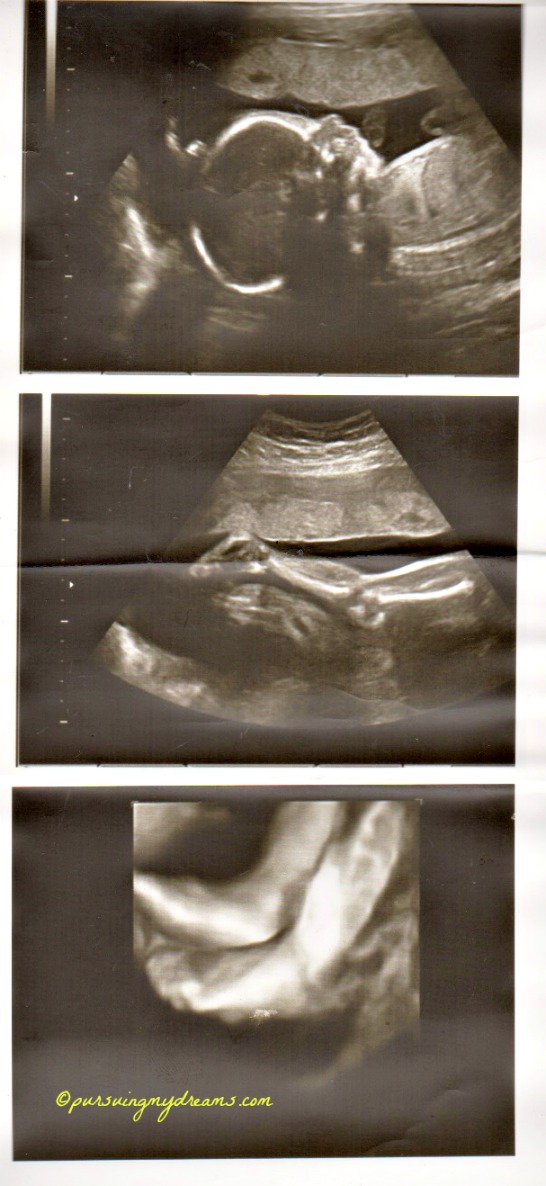

Sebagai penutup saya sertakan foto hasil usg anakku. Ini usg saat usia kehamilan 25 minggu. Dilakukan di kliknik Mannheim. Setelah itu sampai saat ini dokter tidak pernah melakukan pemeriksaan usg lagi karena semuanya baik-baik saja. Jadi hanya diperiksa posisi kandungan.

Iya bang keliatan jelas, padahal itu masih 25 minggu. Ga tau saya usg apa namanya hehehe.

Hidung anakku ngikut aku Ndang alias pesek, dokternya bilang gitu 😆 .

wah… udah kelihatan jelas. itu pake uSG 3 dimensi yah? mirip sama buku ….. ah lupa judulnya… isinya seh kebanyakan foto perkembangan janin di setiap minggunya